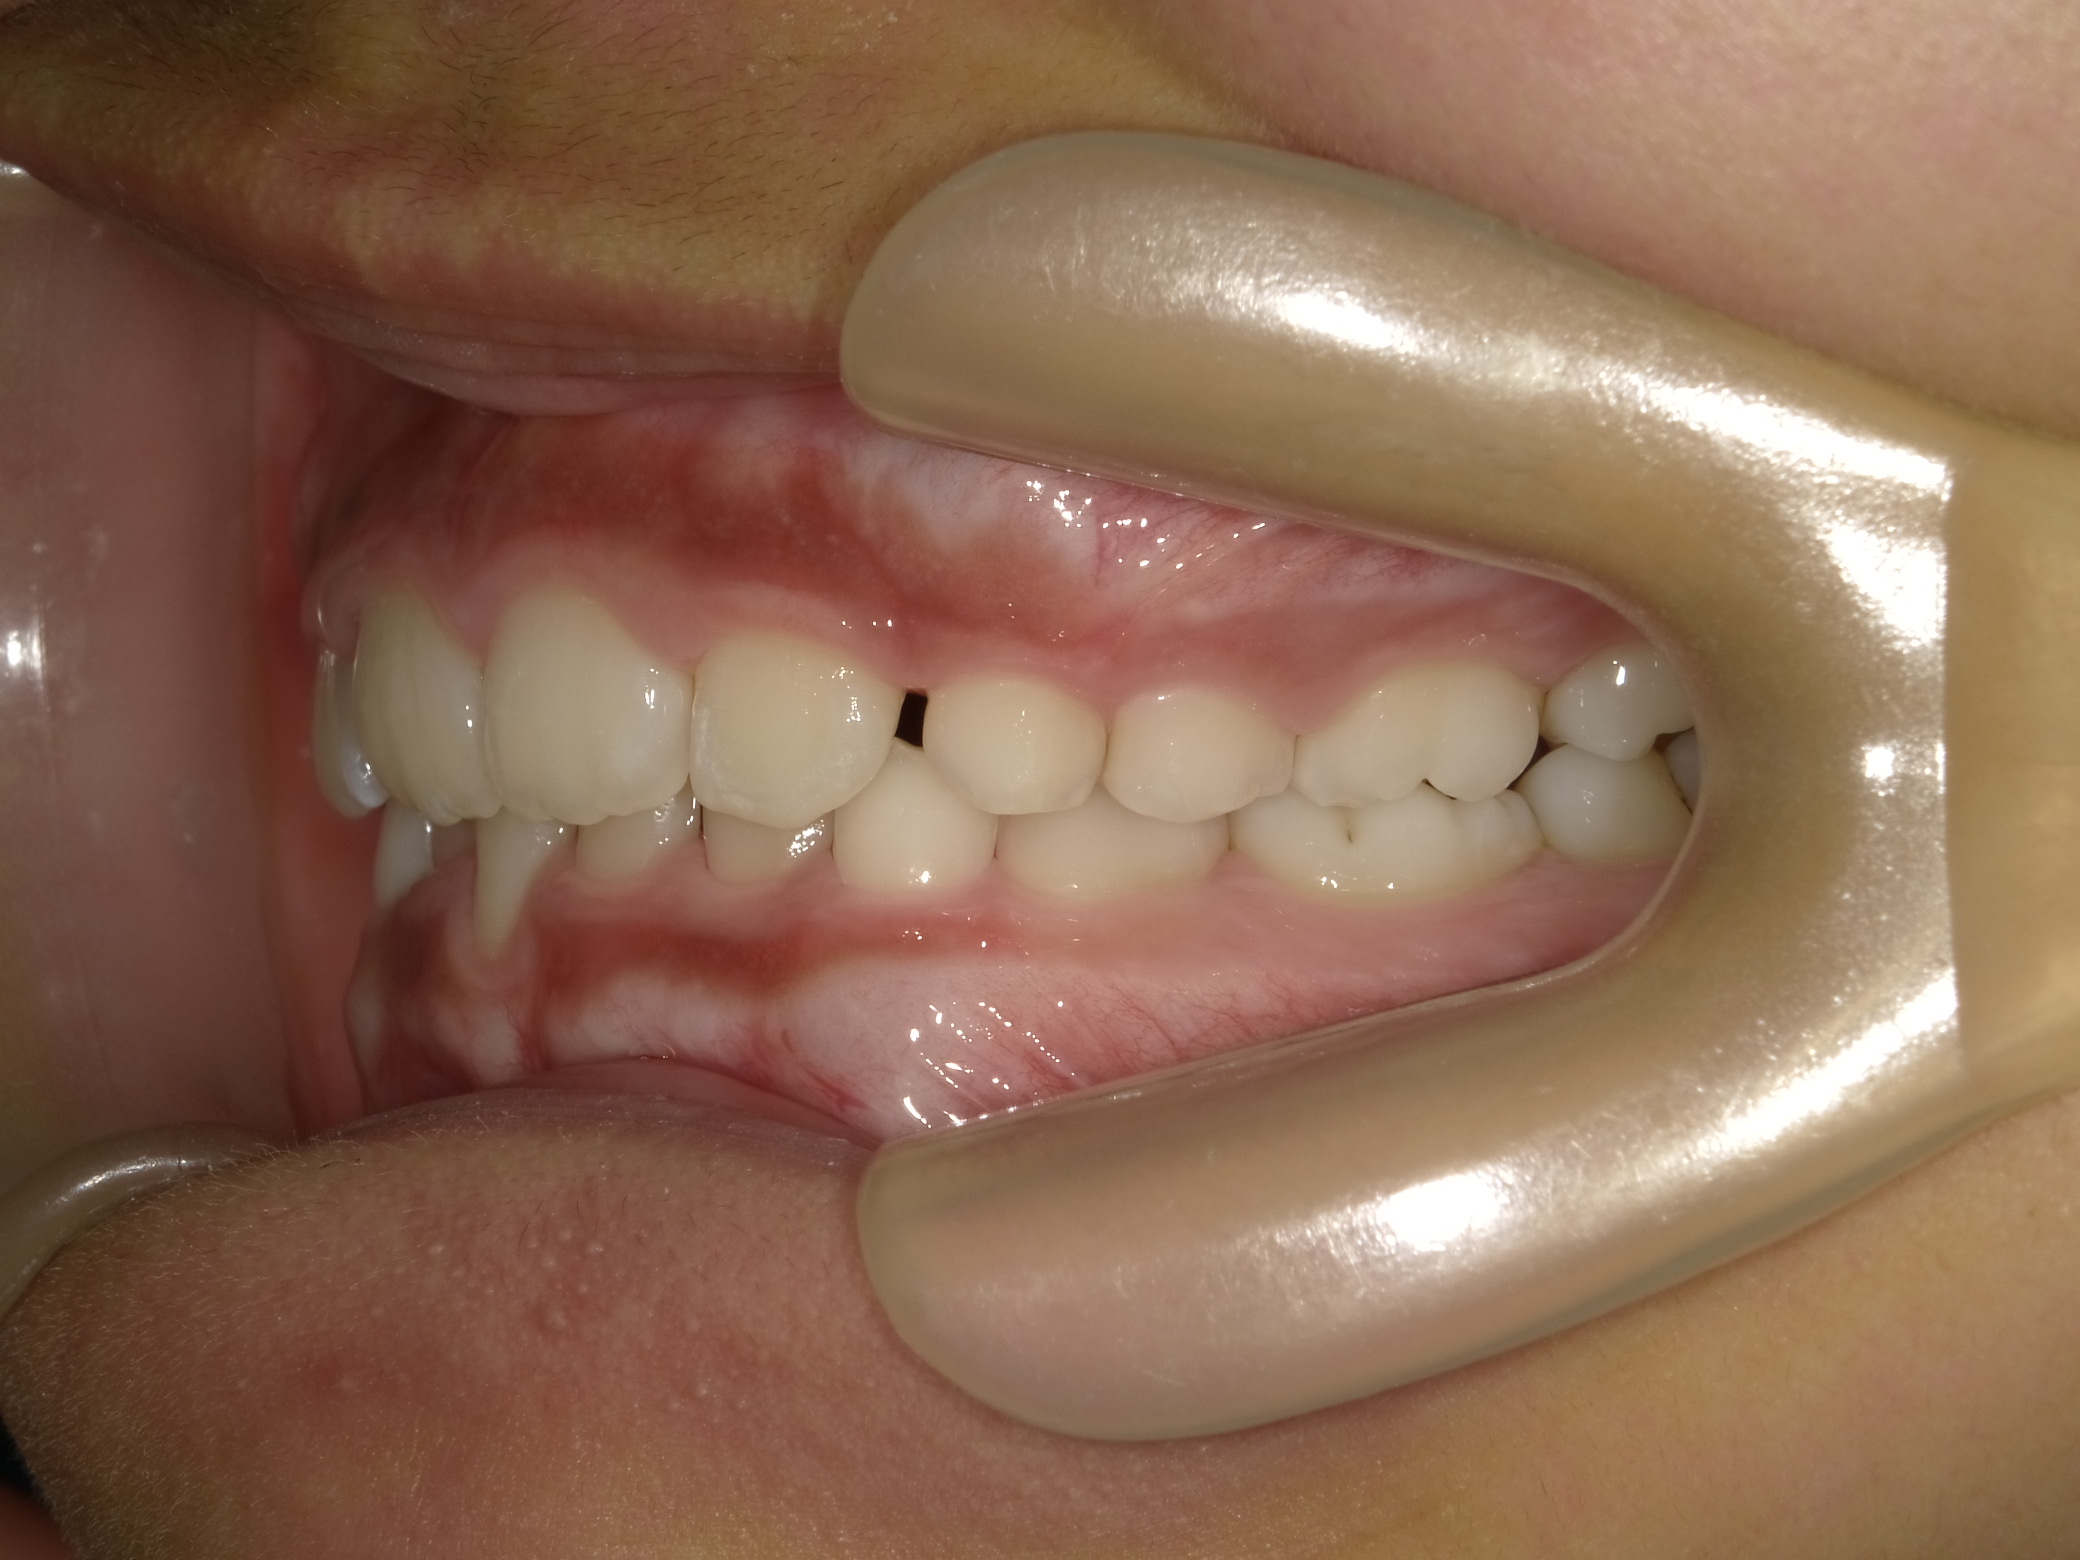

| 症例分類 | 交叉咬合 |

|---|---|

| 主訴 | 前歯がずれて咬んでいる |

| 年齢 | 9歳5ヶ月 |

| 性別 | 女性 |

| 抜歯部位 | なし |

| 使用装置 | 拡大装置、上顎前歯部のセクショナルアーチ装置、取り外し式保定装置 |

| 治療期間 | 1年2ヶ月 |

| 費用 | 相談料0円、検査料50,000円 動的矯正治療費330,000円 調整料6600円×15回分 保定装置料0円 |

| リスク・注意点 | 個々の歯の大きさに対して顎が小さく、歯が並ぶスペースが不足したために交叉咬合が生じています。これらを改善するために、幅の狭搾している歯列を側方に拡大した後、前歯を排列しました。

歯の動き方には個人差があり、予想された治療期間が延長する可能性があります。 治療中は矯正歯科装置が歯の表面に付いており、歯が磨きにくくなるため、むし歯や歯周病が生じるリスクが高まります。ハミガキを適切に行ってお口の中を常に清潔に保ち、さらに、かかりつけ歯科医に定期的に受診することが大切です。 矯正歯科装置の使用状況、定期的な通院など、矯正歯科治療には患者さんの協力が必要であり、それらが治療結果や治療期間に影響します。 治療の経過によっては当初予定していた治療計画を変更する可能性があります。 保定装置の装着時間が十分確保できない場合、歯並びや、咬み合せの「後戻り」が生じる可能性があります。 上下両側第二大臼歯の萌出を観察する必要があります。 |